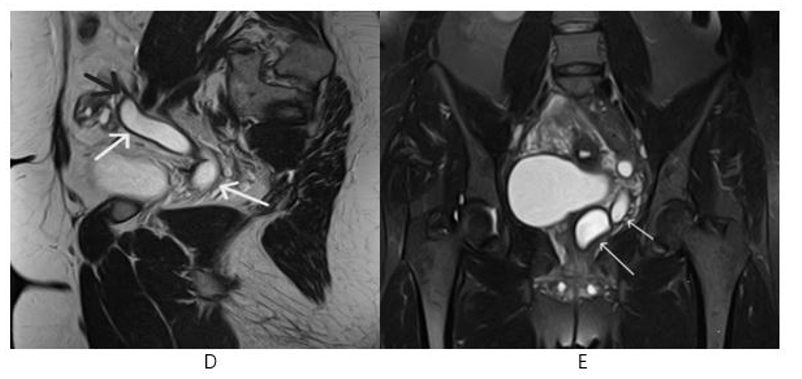

A tubular structure is observed, in left side pelvis extending and opening Gartner’s duct cyst, and ending blindly (Figure 4, Figure 5)

Figure 4, 5: Pelvic MR Non-enhanced Sagital T2 (D) Image: Tubular structure ( White Arrows) Ending blindly (Black Arrow) and Coronal STIR (E) Image: Gartner’s Duct Cyst (Long Arrow) and Tubular Structure (Short Arrow)

Figure 6: Pelvic MR Non-Enhanced Axial T2 (F) Tubular Structure ( White Short Arrow) and Gartner’s duct cyst (White Long Arrow)